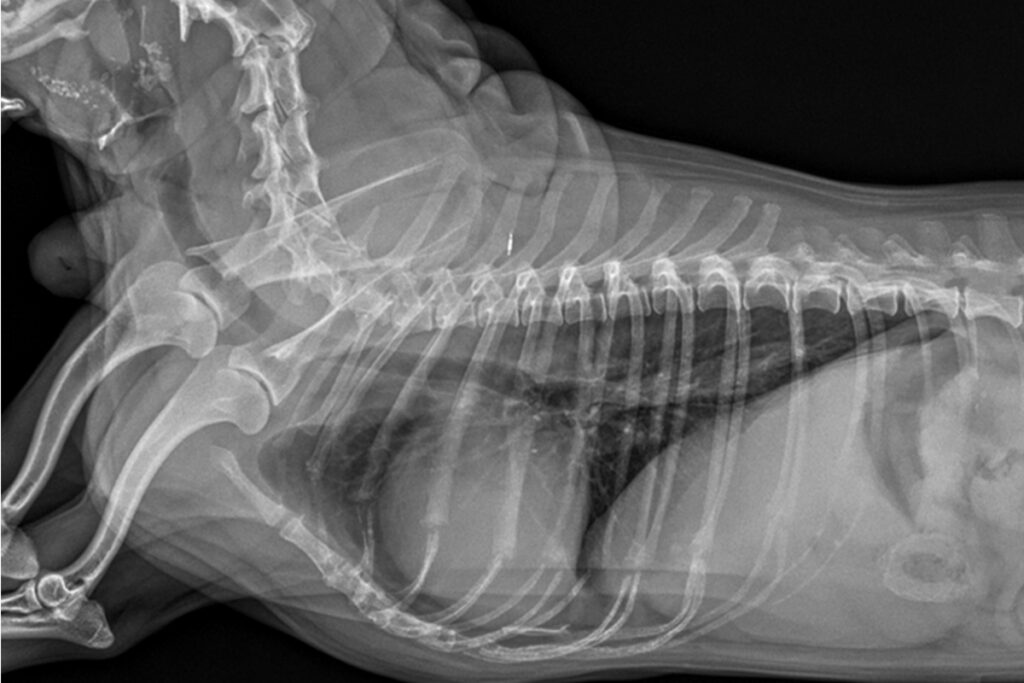

자궁축농증 수술

자궁 내 감염으로 생명을 위협할 수 있는 응급 질환입니다. 조기 수술과 수술 전·후 집중 관리가 예후에 매우 중요합니다.